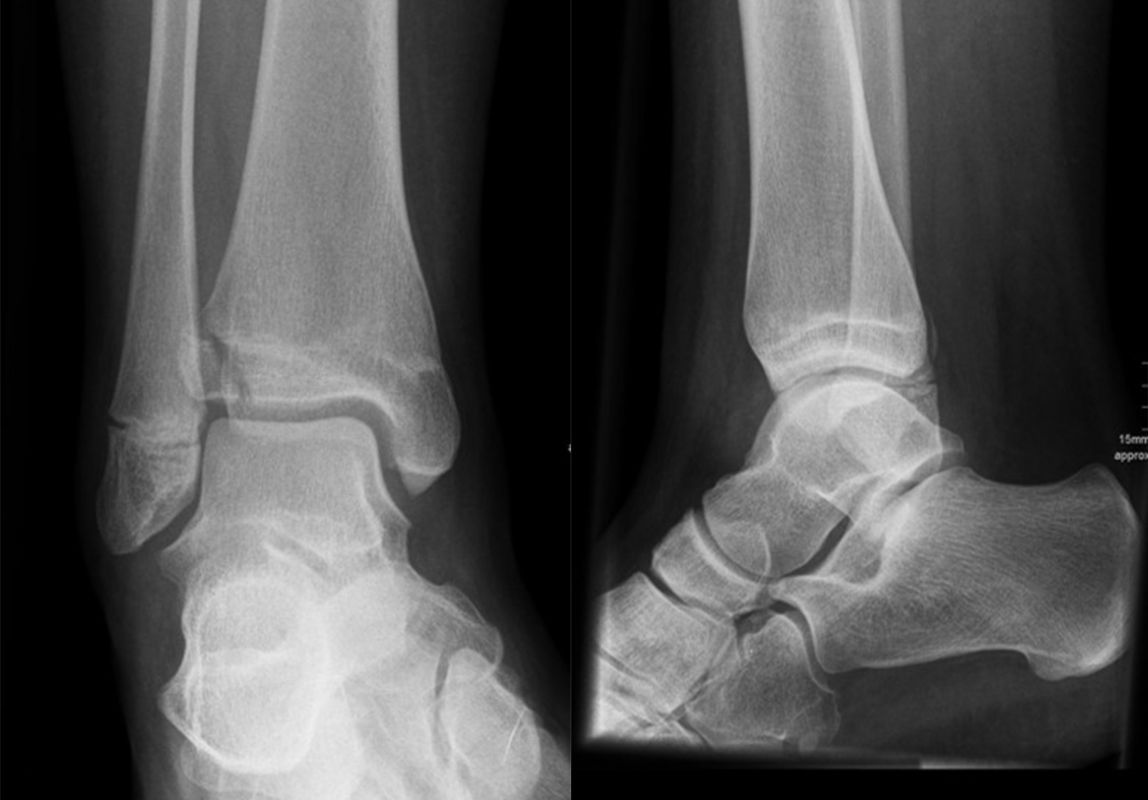

Die Standard Röntgendiagnostik des Sprunggelenks umfasst Bilder in anteriorposterioren (a.p.) und im seitlichen Strahlengang 6. Für die exakte Abbildung des Innenknöchels müssen beide Malleolen parallel zur Röntgenplatte zu liegen kommen. Je nach Torsion der Tibia macht dies eine Innenrotation des Fußes zwischen 10° und 30° erforderlich (Abb. 3).

Manchmal sind mediale Malleolarfrakturen nur in einer der Aufnahmen in ihrem Ausmaß erkennbar. Keine Rolle spielt die gehaltene Aufnahme beim Kind, insbesondere bei der akuten Verletzung. In seltenen Fällen hat dieses Verfahren bei Verdacht auf eine chronische Instabilität eine Berechtigung.

Fugengelenkfrakturen treten typischerweise vor dem 10. Lebensjahr auf, in einer Phase, in welcher die Wachstumsfugen noch weit offen sind. Dieser Frakturtyp betrifft fast ausschließlich den medialen Malleolus. Laterale Frakturen sind extrem selten, teilweise kommt es zu lateralen Bandverletzungen oder Fugenschaftfrakturen der distalen Fibula. Die Frakturlinie verläuft in einer Verlängerungslinie von der medialen Taluskante nach proximal. Häufig stellen sich Verletzungen des Innenknöchels im Röntgenbild schlechter dar, insbesondere wenn die Aufnahmen verdreht sind oder die Ebene der Fraktur bei geringer Dislokation verkippt zur Röntgenebene liegt. Besteht klinisch der geringste Hinweis auf eine Verletzung des Innenknöchels, muss aufgrund der Tragweite der Verletzung durch entsprechende Aufnahmen gegebenenfalls auch Schnittbildverfahren die Verletzung sicher diagnostiziert oder ausgeschlossen werden (Abb. 15).